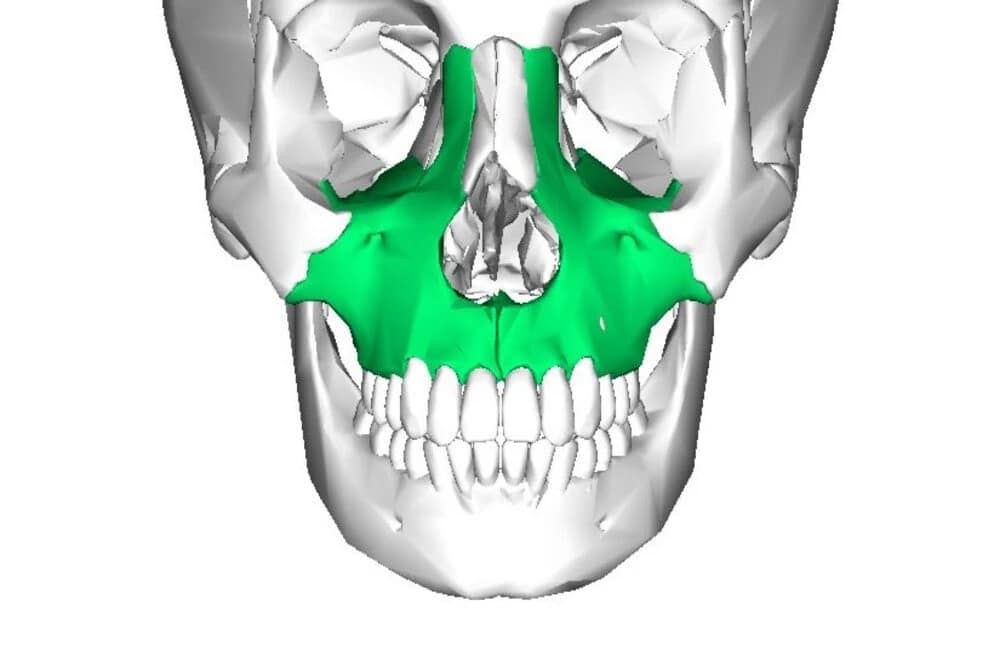

La Zona de Atención en el Maxilar Superior

El maxilar superior presenta riesgos diferentes, principalmente relacionados con las cavidades aéreas:

La Zona de Atención en el Maxilar Superior

El seno maxilar es una cavidad llena de aire que se encuentra sobre las raíces de los molares y premolares superiores. Al perder dientes, el hueso disponible bajo el seno (cresta alveolar) se reabsorbe y la cavidad del seno se expande

- La Zona de Seguridad: El implante debe quedar alojado en hueso sólido. Si el hueso remanente es insuficiente (menos de 5-6 mm), no podemos colocar el implante directamente.

- La Solución: Aquí es donde entra en juego la experiencia en técnicas avanzadas como el Elevamiento de Seno Maxilar (Sinus Lift). Esta cirugía controlada permite regenerar hueso en la base del seno, restaurando la Zona de Seguridad y permitiendo la colocación segura de un implante más largo.

- Riesgo por Incumplimiento: Perforar la membrana de Schneider (el revestimiento del seno) puede resultar en una comunicación bucosinusal o una sinusitis.

La Cavidad Nasal

En los implantes anteriores, cerca de los incisivos, debemos respetar la cavidad nasal.

- La Zona de Seguridad: El implante debe quedar lejos del piso nasal. La planificación es clave para mantener la punta del implante dentro del hueso sin invadir esta cavidad.